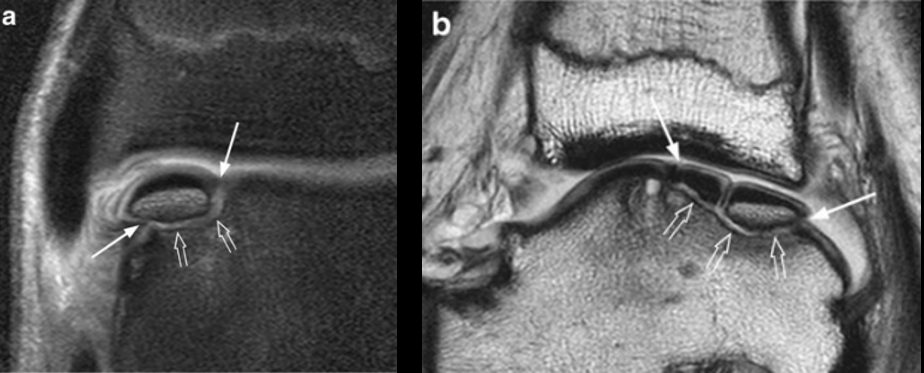

Рис. 8. МРТ: стадии 5а и 5б — субхондральная киста (хроническое повреждение)